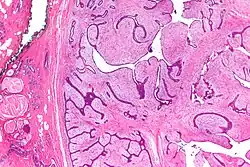

| Micrograph of a phyllodes tumor (right of image) with the characteristic long clefts and myxoid cellular stroma. Normal breast and fibrocystic change are also seen (left of image). H&E stain. |

Phyllodes tumors (from Greek: phullon), are a rare type of biphasic fibroepithelial mass that form from the periductal stromal and epithelial cells of the breast.[1] They account for less than 1% of all breast neoplasms.[2] They were previously termed cystosarcoma phyllodes, coined by Johannes Müller in 1838, before being renamed to phyllodes tumor by the World Health Organization in 2003.[3] Phullon, which means 'leaf' in Greek, describes the unique papillary projections characteristic of phyllodes tumors on histology.[1] Diagnosis is made via a core-needle biopsy and treatment is typically surgical resection with wide margins (>1 cm), due to their propensity to recur.[4]